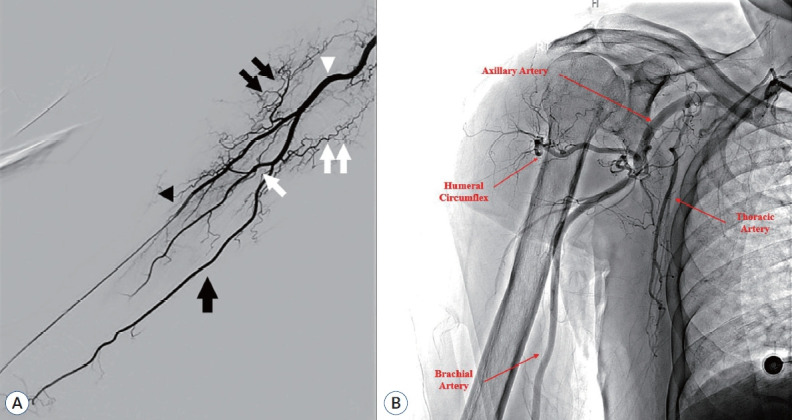

The femoral artery is the preferred access route for neurointerventions. The transfemoral approach (TFA) offers advantages such as a large diameter and easy access. However, it also entails disadvantages such as patient discomfort and high risk of complications. Following the initial report of coronary angiography using the transradial approach (TRA) in 1989, cardiologists discovered the advantages of TRA over the TFA and gradually replaced it with the TRA. In 1997, Matsumoto et al. used the TRA for cerebral angiography and neurointervention. Thereafter, the adoption of TRA for neurointervention gradually increased and good outcomes were reported. However, despite these developments, the adoption rate of TRA is relatively low. We reviewed the relevant studies to increase the accessibility of TRA for neurointerventionists.